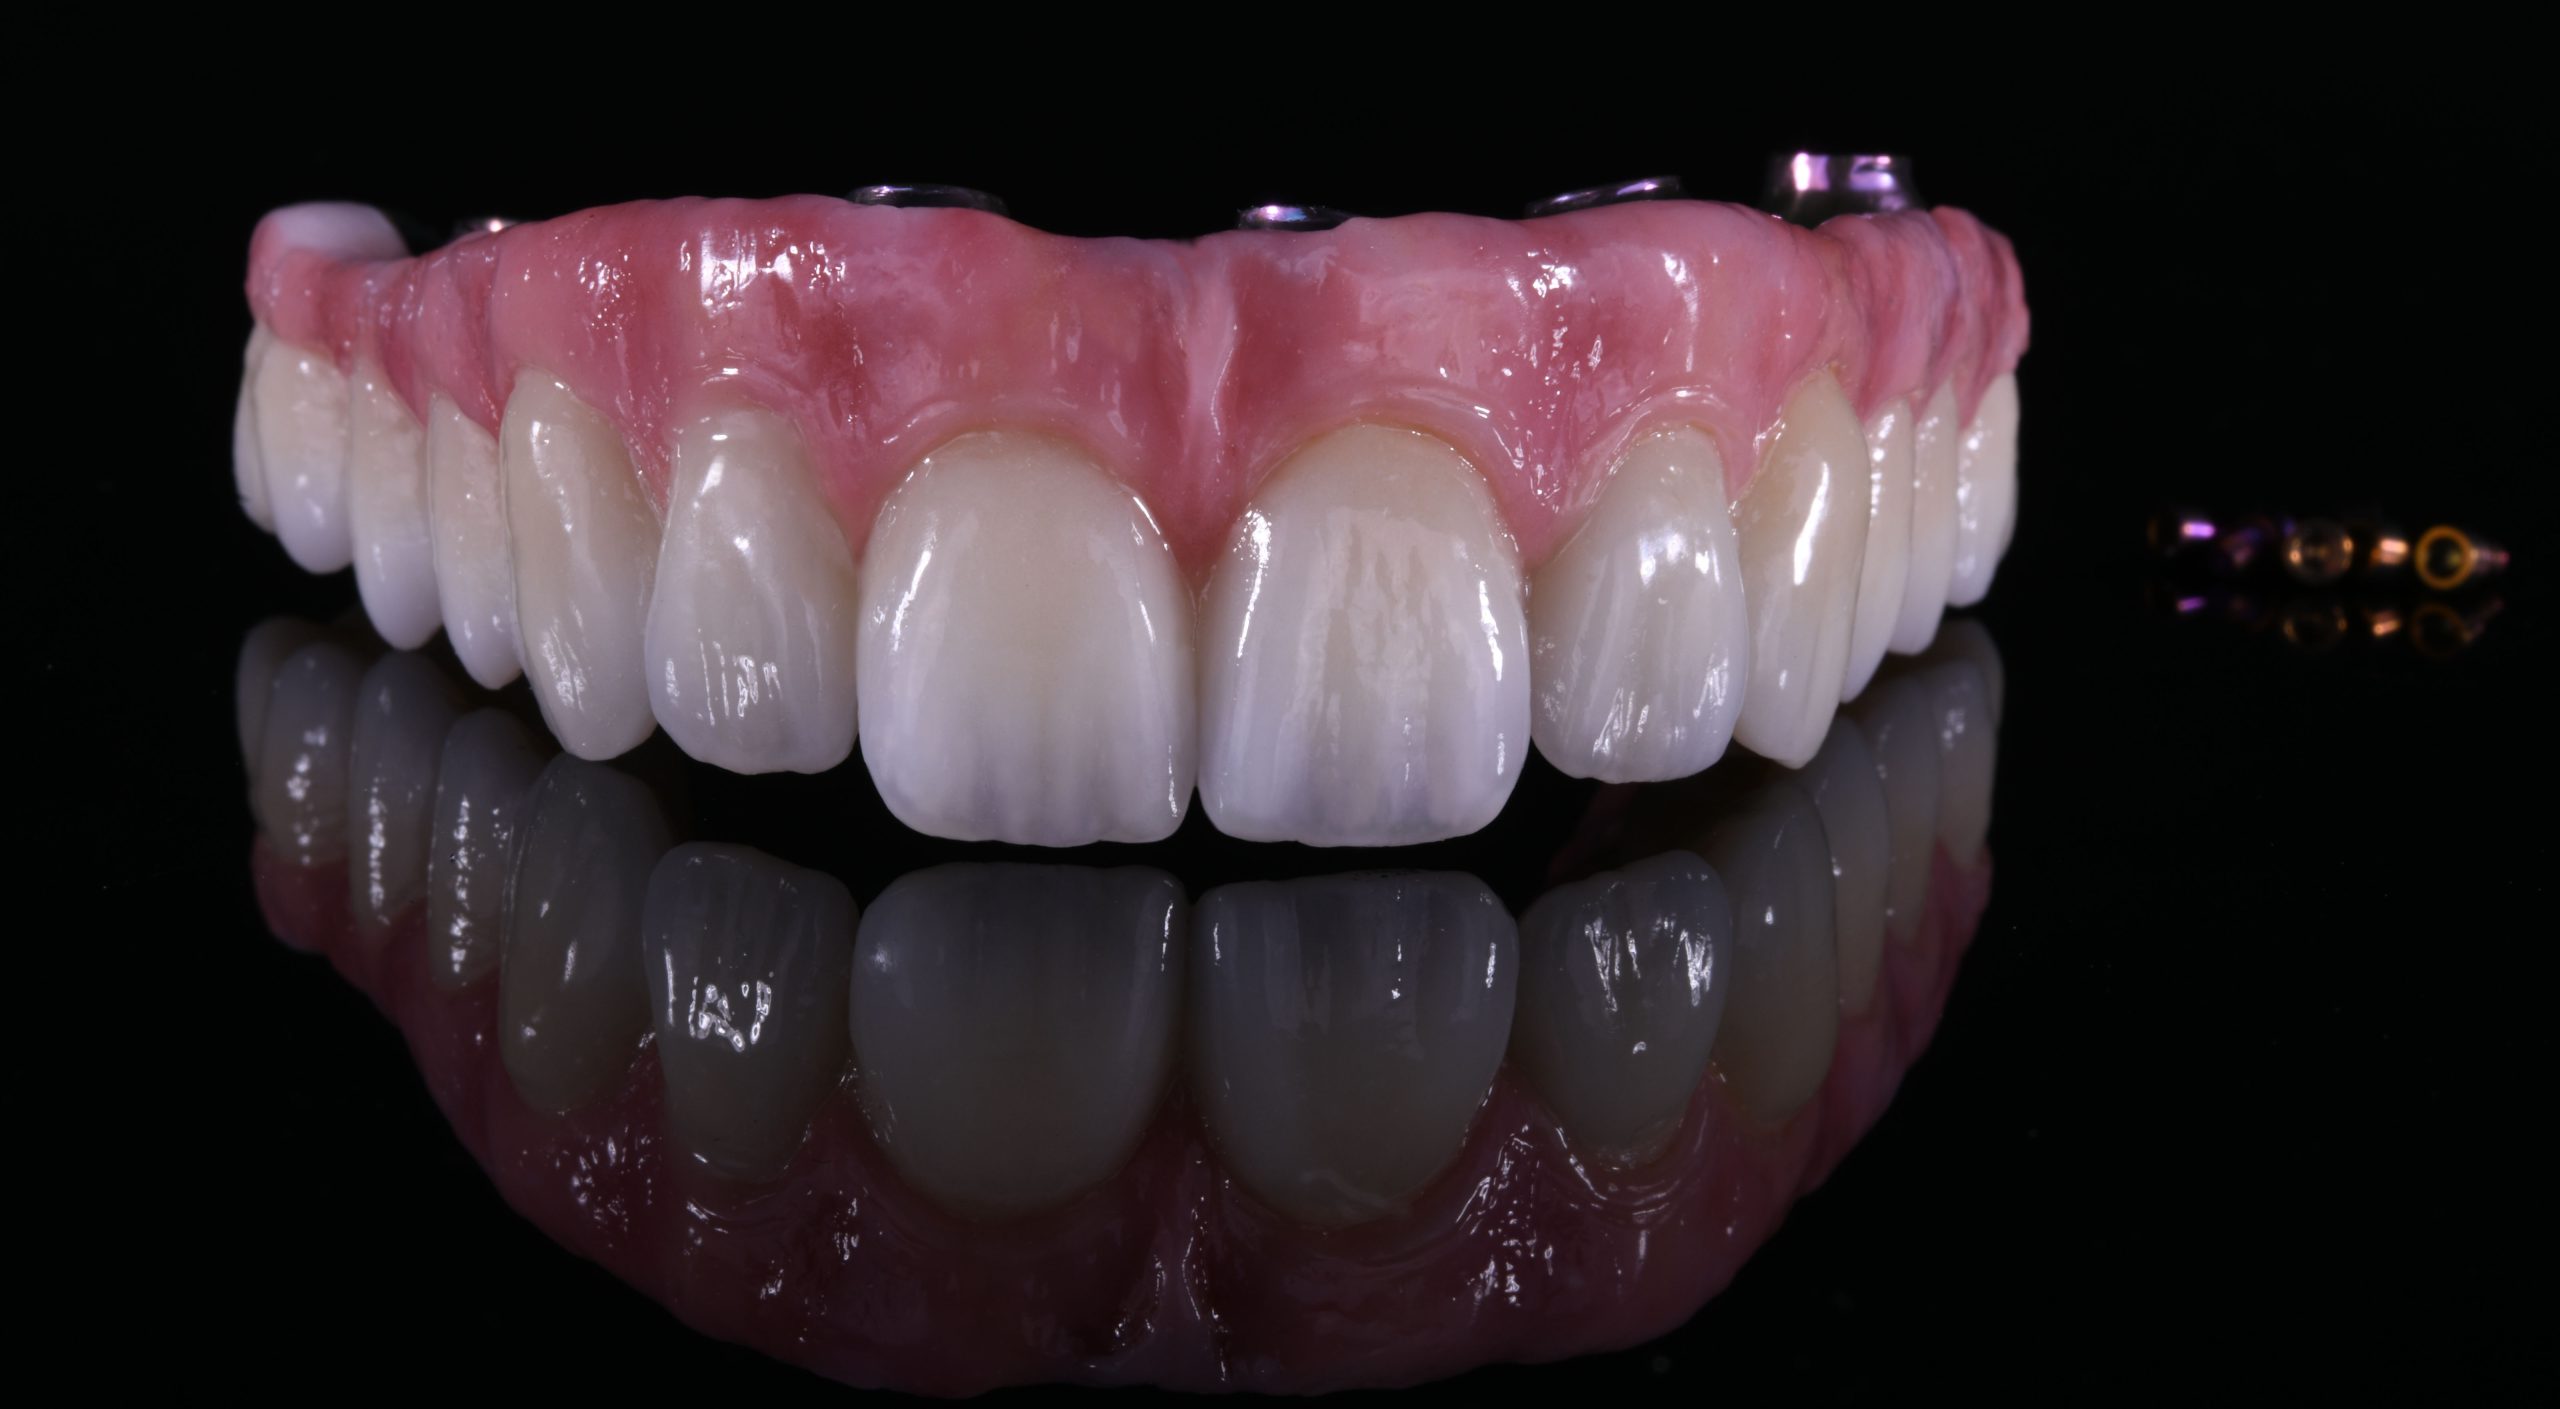

Complete upper rehabilitation directly screwed in zirconia – ceramic

The use of CDP (Complete Digital Patient) as a basis for planning in a case of complete implant rehabilitation with a full arch in zirconia – ceramicised

Total upper and lower rehabilitation in zirconia on implants with titanium reinforcement bars

Complete Digital Patient (CDP): guided surgery for complete upper and lower rehabilitation with zirconia-ceramic screw-retained implants